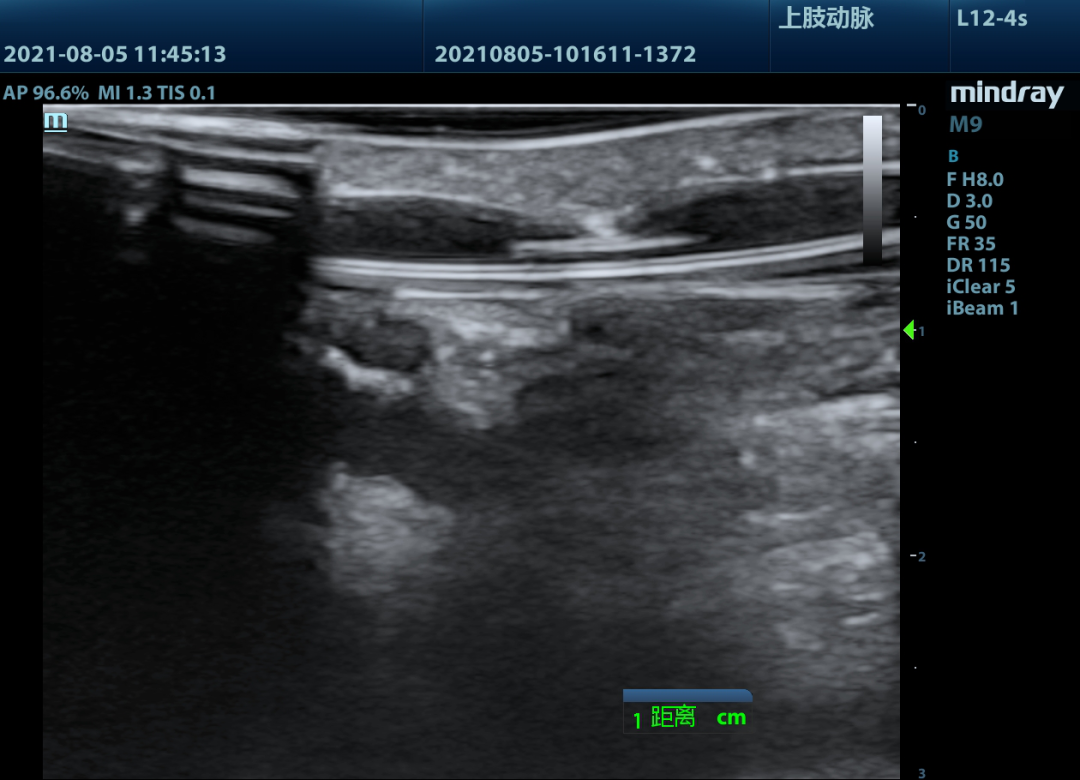

▲头静脉血管节段狭窄